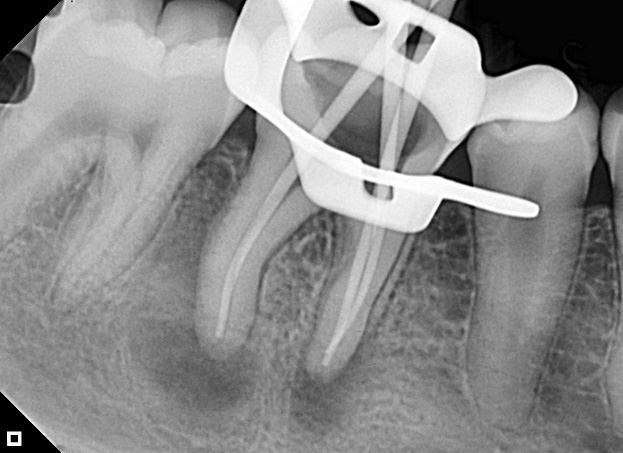

The filling was carried out with Bio-C Sealer bioceramic endodontic cement (Angelus) (Figure 3A). The cement was inserted into the canals using the product’s supplied tips, 4 mm below the working length, and dispensed slightly up to the cervical third. After inserting the cement, gutta-percha cones were inserted and filled using the hydraulic compression technique (Figure 3B).

Figure 3: Obturation Cement (A)

Figure 3: Final radiograph (B)